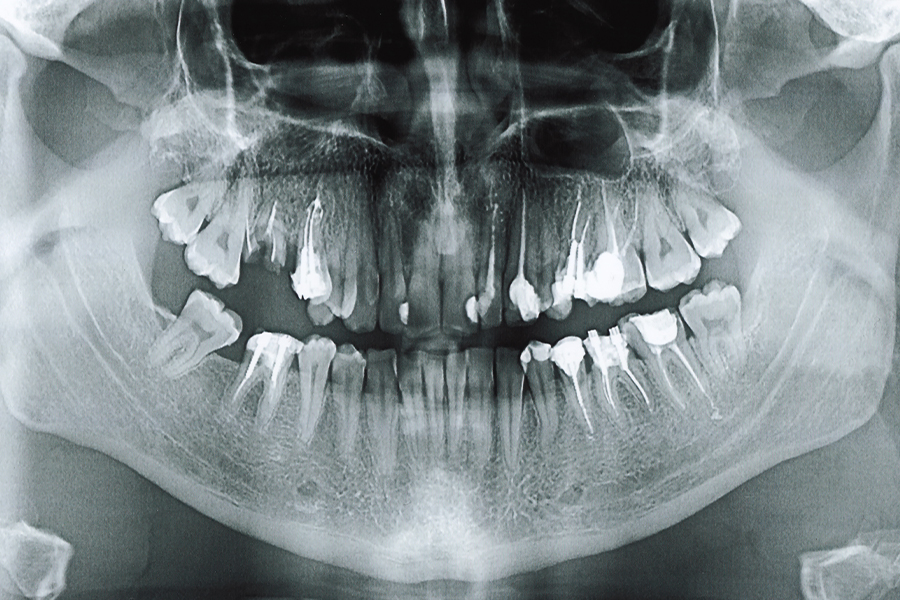

デンタルエックス線写真撮影

肉眼では見えない歯の根や顎の状態なども確認できる写真を撮影します。

当院では、お口全体を1枚で写す「パノラマエックス線写真」と、細分化してより詳しく写す「10枚法」という撮影方法を用います。

10枚法は小さなむし歯や異変を見つけやすくなるので、パノラマエックス線写真と組み合わせて、的確で精密に現状を把握できます。